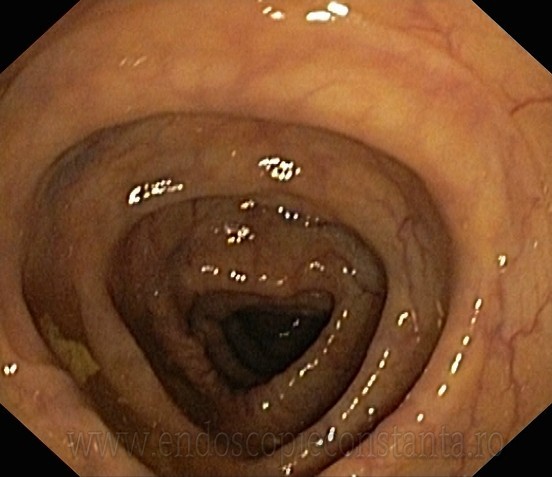

COLONOSCOPIE

Colonoscopia permite examinarea directa a interiorului intestinului gros. Examinarea se face cu un aparat optic ( colonoscop ) , care se introduce in tractul digestiv inferior , fiind manevrat pentru a ajunge in portiunea cea mai proximala a intestinului gros (cec) , si uneori si in ultima portiune a intestinului subtire (ileon terminal ) , fiind apoi retras , efectuindu-se in acest timp o examinare atenta.